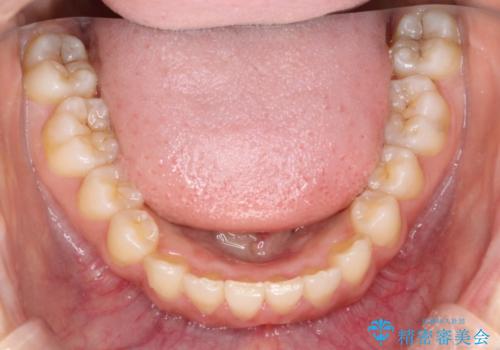

インビザラインを使用した深いかみ合わせの矯正

- 前歯のガタガタを主訴に来院された患者様です。

八重歯になっており、下顎の前歯が上顎の前歯に隠れてしまう、ディープバイトという状態でした。

インビザラインを使用して矯正する計画としました。

ディープバイトの場合、ワイヤー装置の装着が難しいことがあります。

インビザラインではかみ合わせに左右されず装着できるメリットがあり、ワイヤーに比べインビザラインの方が治療しやすい場合もあります。